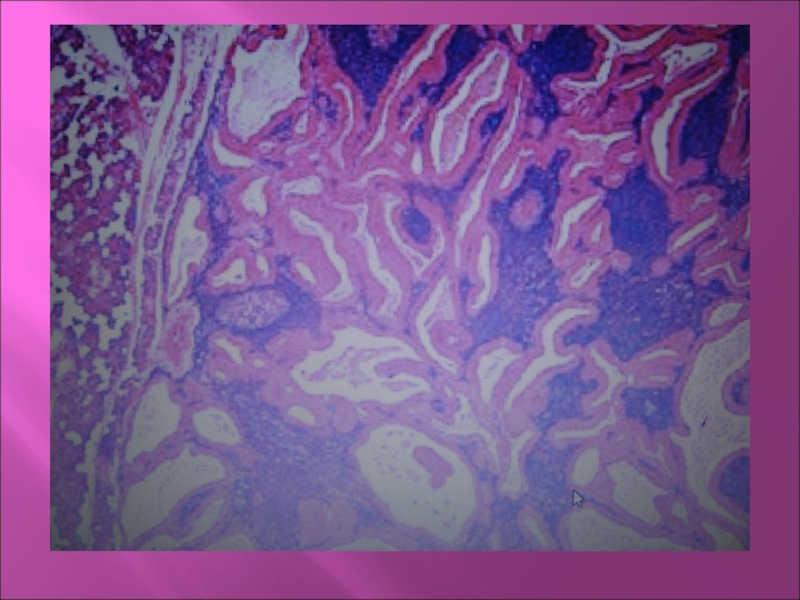

Макро: Узел округлой формы, бугристый,

плотный или эластичный, размер 5-6 см., окружен капсулой. На разрезе ткань белая с хрящевидными и слизистыми участками, кистами.

Микро: разнообразна, эпителиальные клетки имеют структуру протоков, солидных полей, гнезд. Есть скопления вытянутых клеток, полей мукоидного, миксоидного и хондроидного вещества.